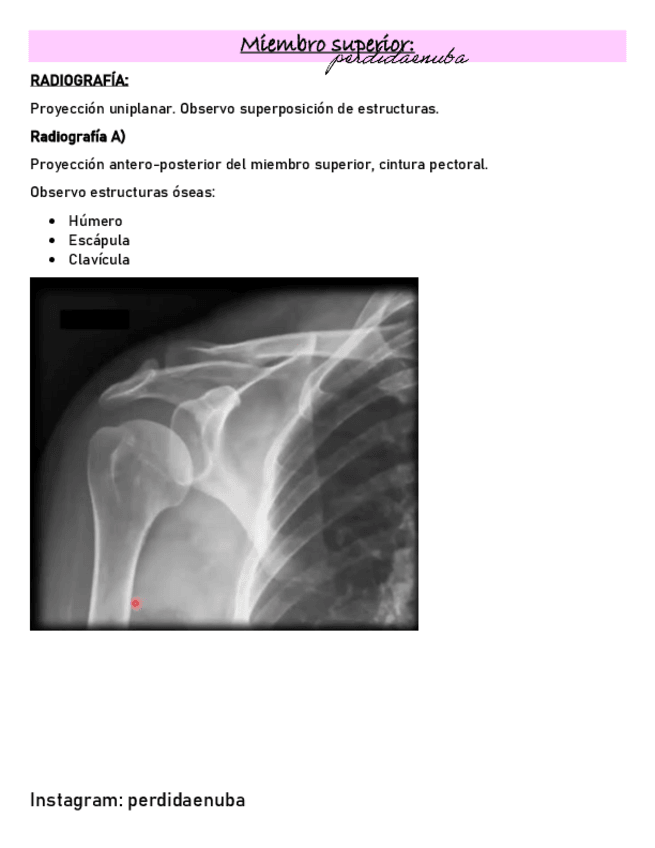

He publicado nuevos apuntes de 8º Cirugía General: CINTURA-PECTORAL-1.pdf